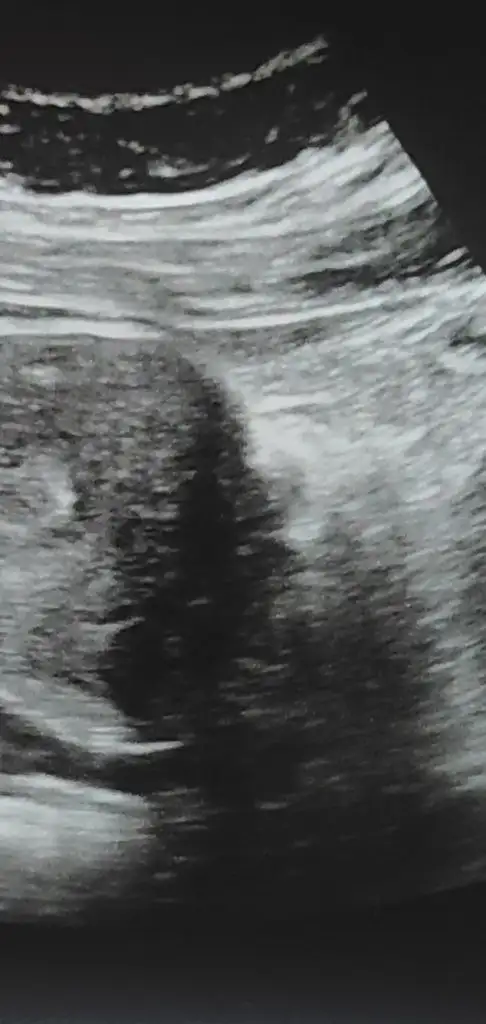

Bende de kimyasal olmuştu. Doktor şu an ölçüme gerek yok gayet güzel yerde dış gebelik de değil dedi 18 ine gel kalbini duyalım tekrar beta da istemedi. İçini ferah tut. Ultrasonun üstünde 12 cm yazıyo ama o başka bir şeydir mümkün değil o kadar olması zatenHmm anladım canım bende daha keseyi görebildim ancak ilk gebeliğimde boş gebelik oldu bundada korkuyorum bide kesen kaç mm biliyormsn

1.2 cm yazıyordur sanırımBende de kimyasal olmuştu. Doktor şu an ölçüme gerek yok gayet güzel yerde dış gebelik de değil dedi 18 ine gel kalbini duyalım tekrar beta da istemedi. İçini ferah tut. Ultrasonun üstünde 12 cm yazıyo ama o başka bir şeydir mümkün değil o kadar olması zaten

ben hic anlamiyorum canim .ikiz olsa ne guzel olur :)Kızlar iki tane mi yolk kesesi var ? Doktor emin konuşmadı ama ikiz olabilir dedi. Anlayan varsa yorumlayabilir mi

Benim bildiğim yolk kesesi bir tane olur büyük ihtimalle ikiz o zaman gözünüz aydınKızlar iki tane mi yolk kesesi var ? Doktor emin konuşmadı ama ikiz olabilir dedi. Anlayan varsa yorumlayabilir mi